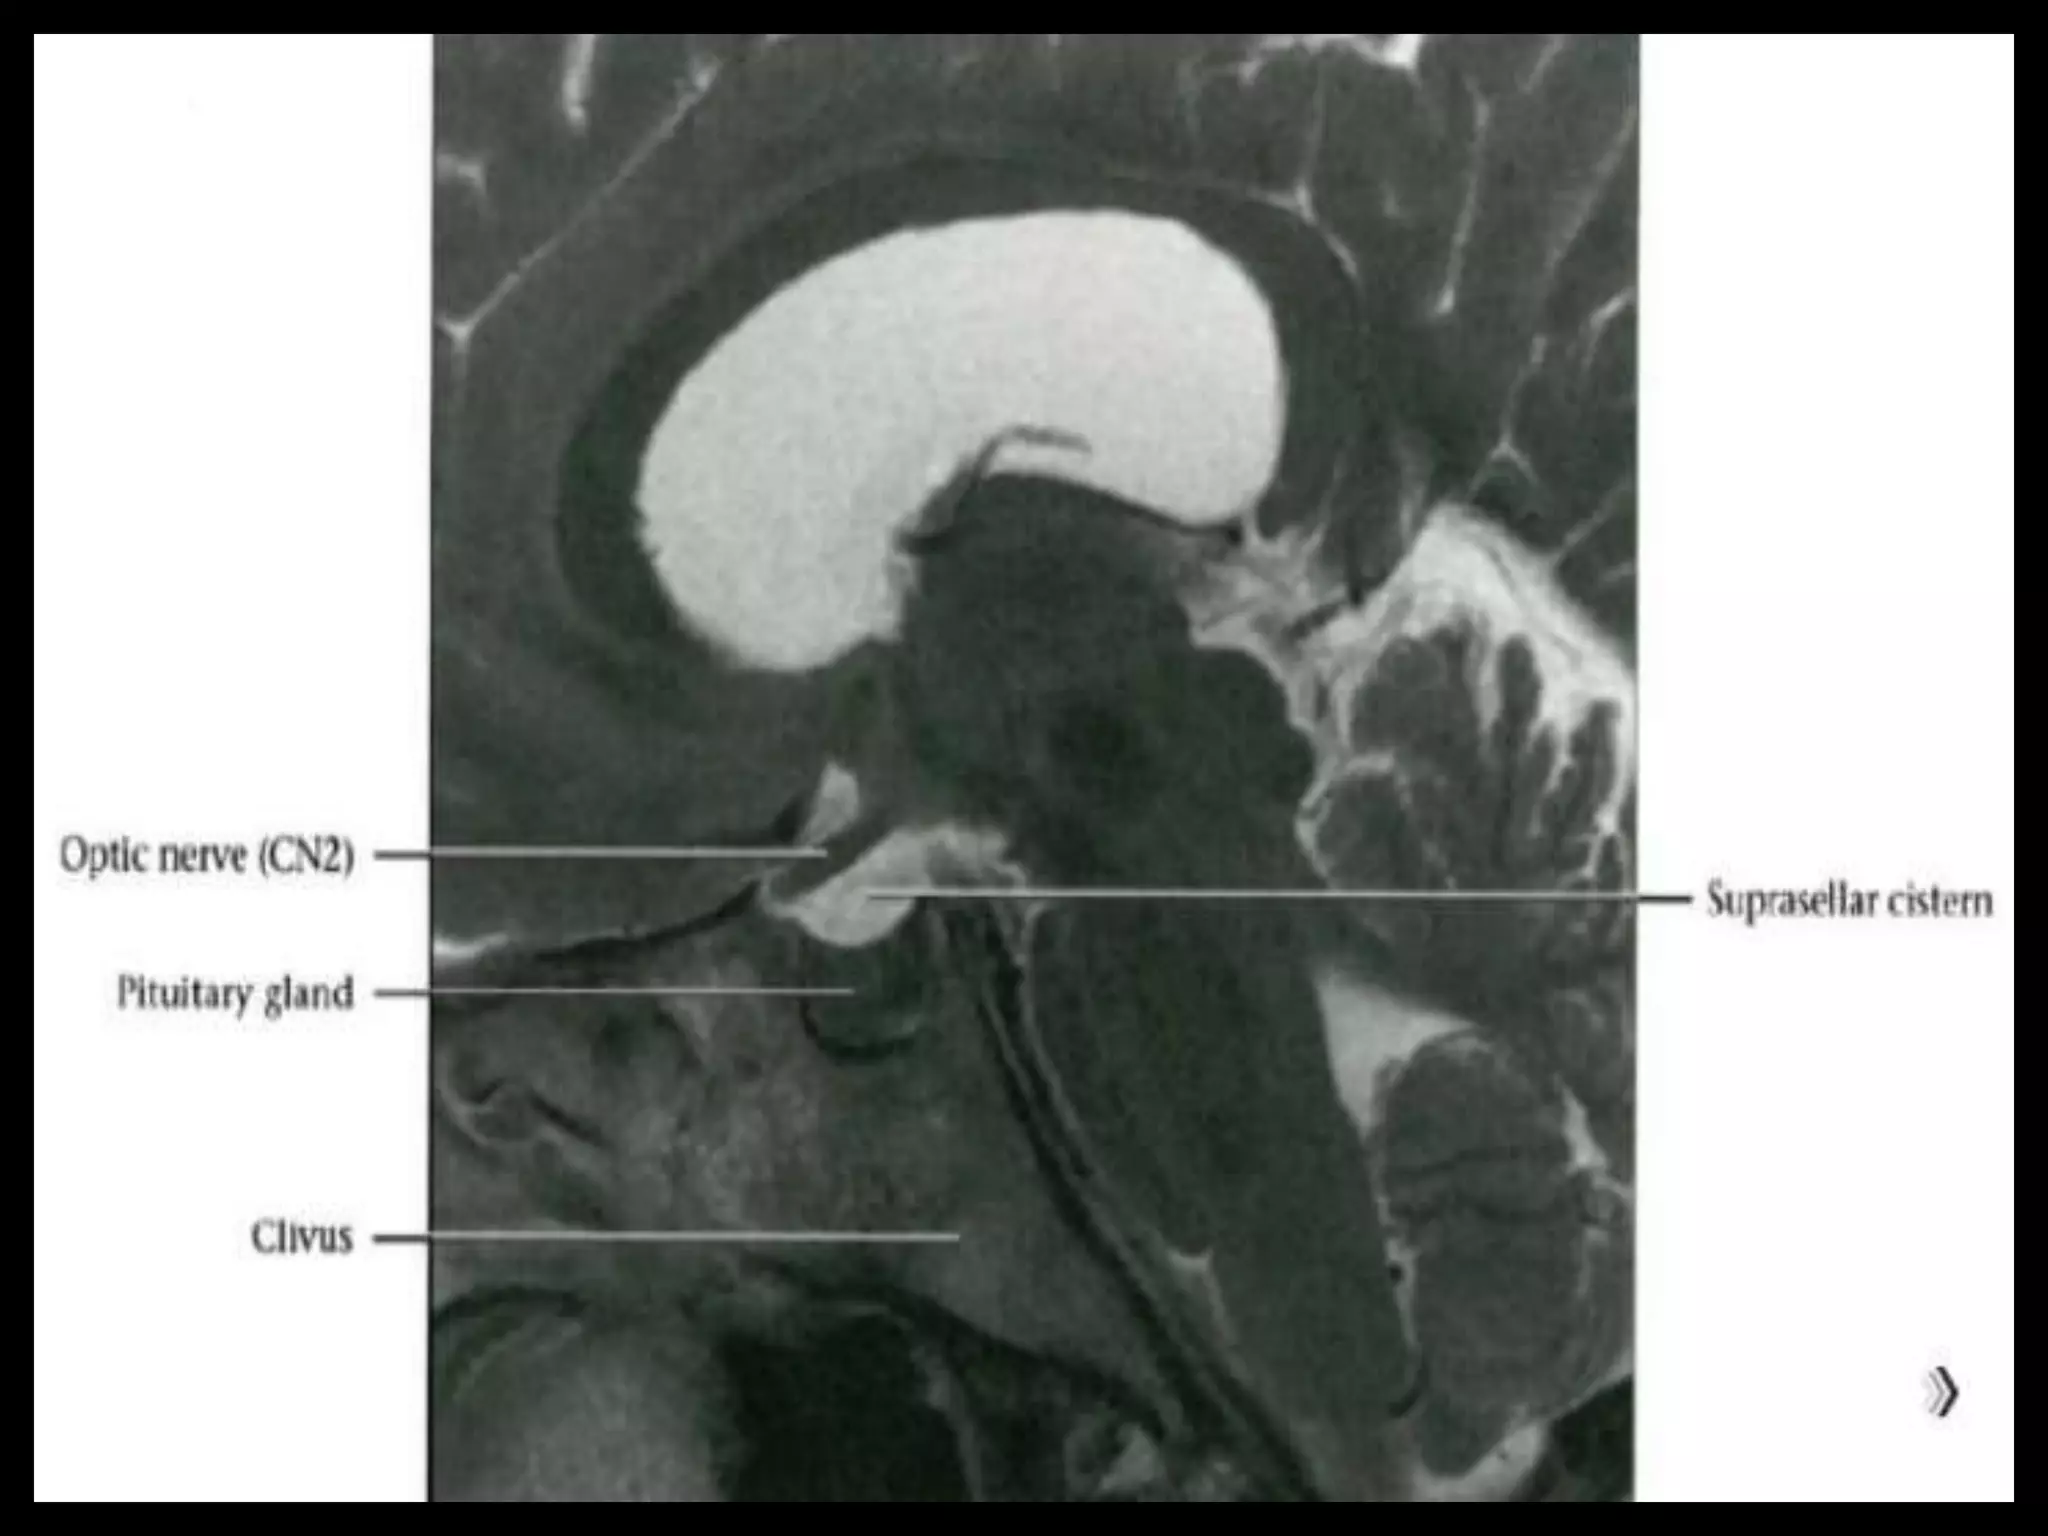

Pituitary Fossa.

Suprasellar Cistern

And Optic Apparatus.

Suprasellar Cistern AndOptic Apparatus.